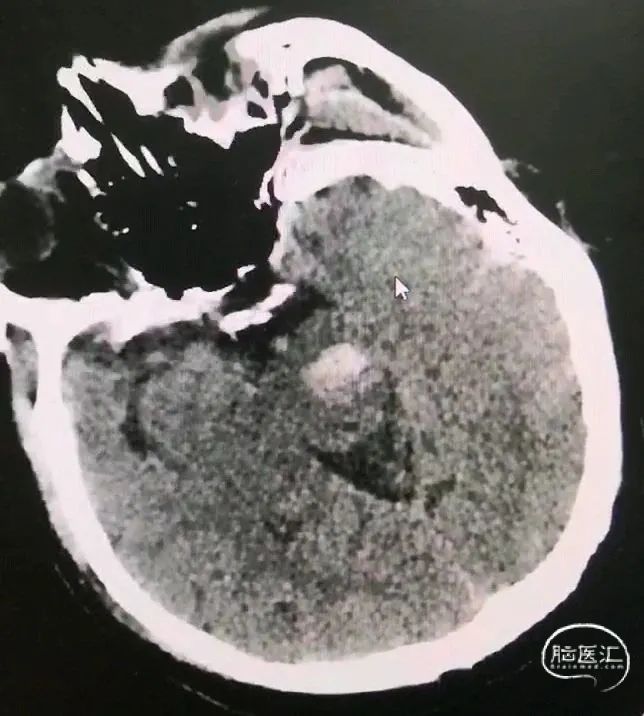

脑干出血往往合并中脑导水管的梗阻,经额入路可术中同步并行放置脑室引流管,经小脑入路可术中经枕叶放置脑室引流管;尤其对于脑室未扩张的病例,利用立体定向框架可准确植入脑室引流管。

一口双孔,平行植入脑室引流管,测算脑室引流管植入靶点

脑室及血肿腔平行双管

引流管穿经中脑血肿

引流管准确到达靶点

术后尿激酶应用,术后3天复查CT,血肿引流满意